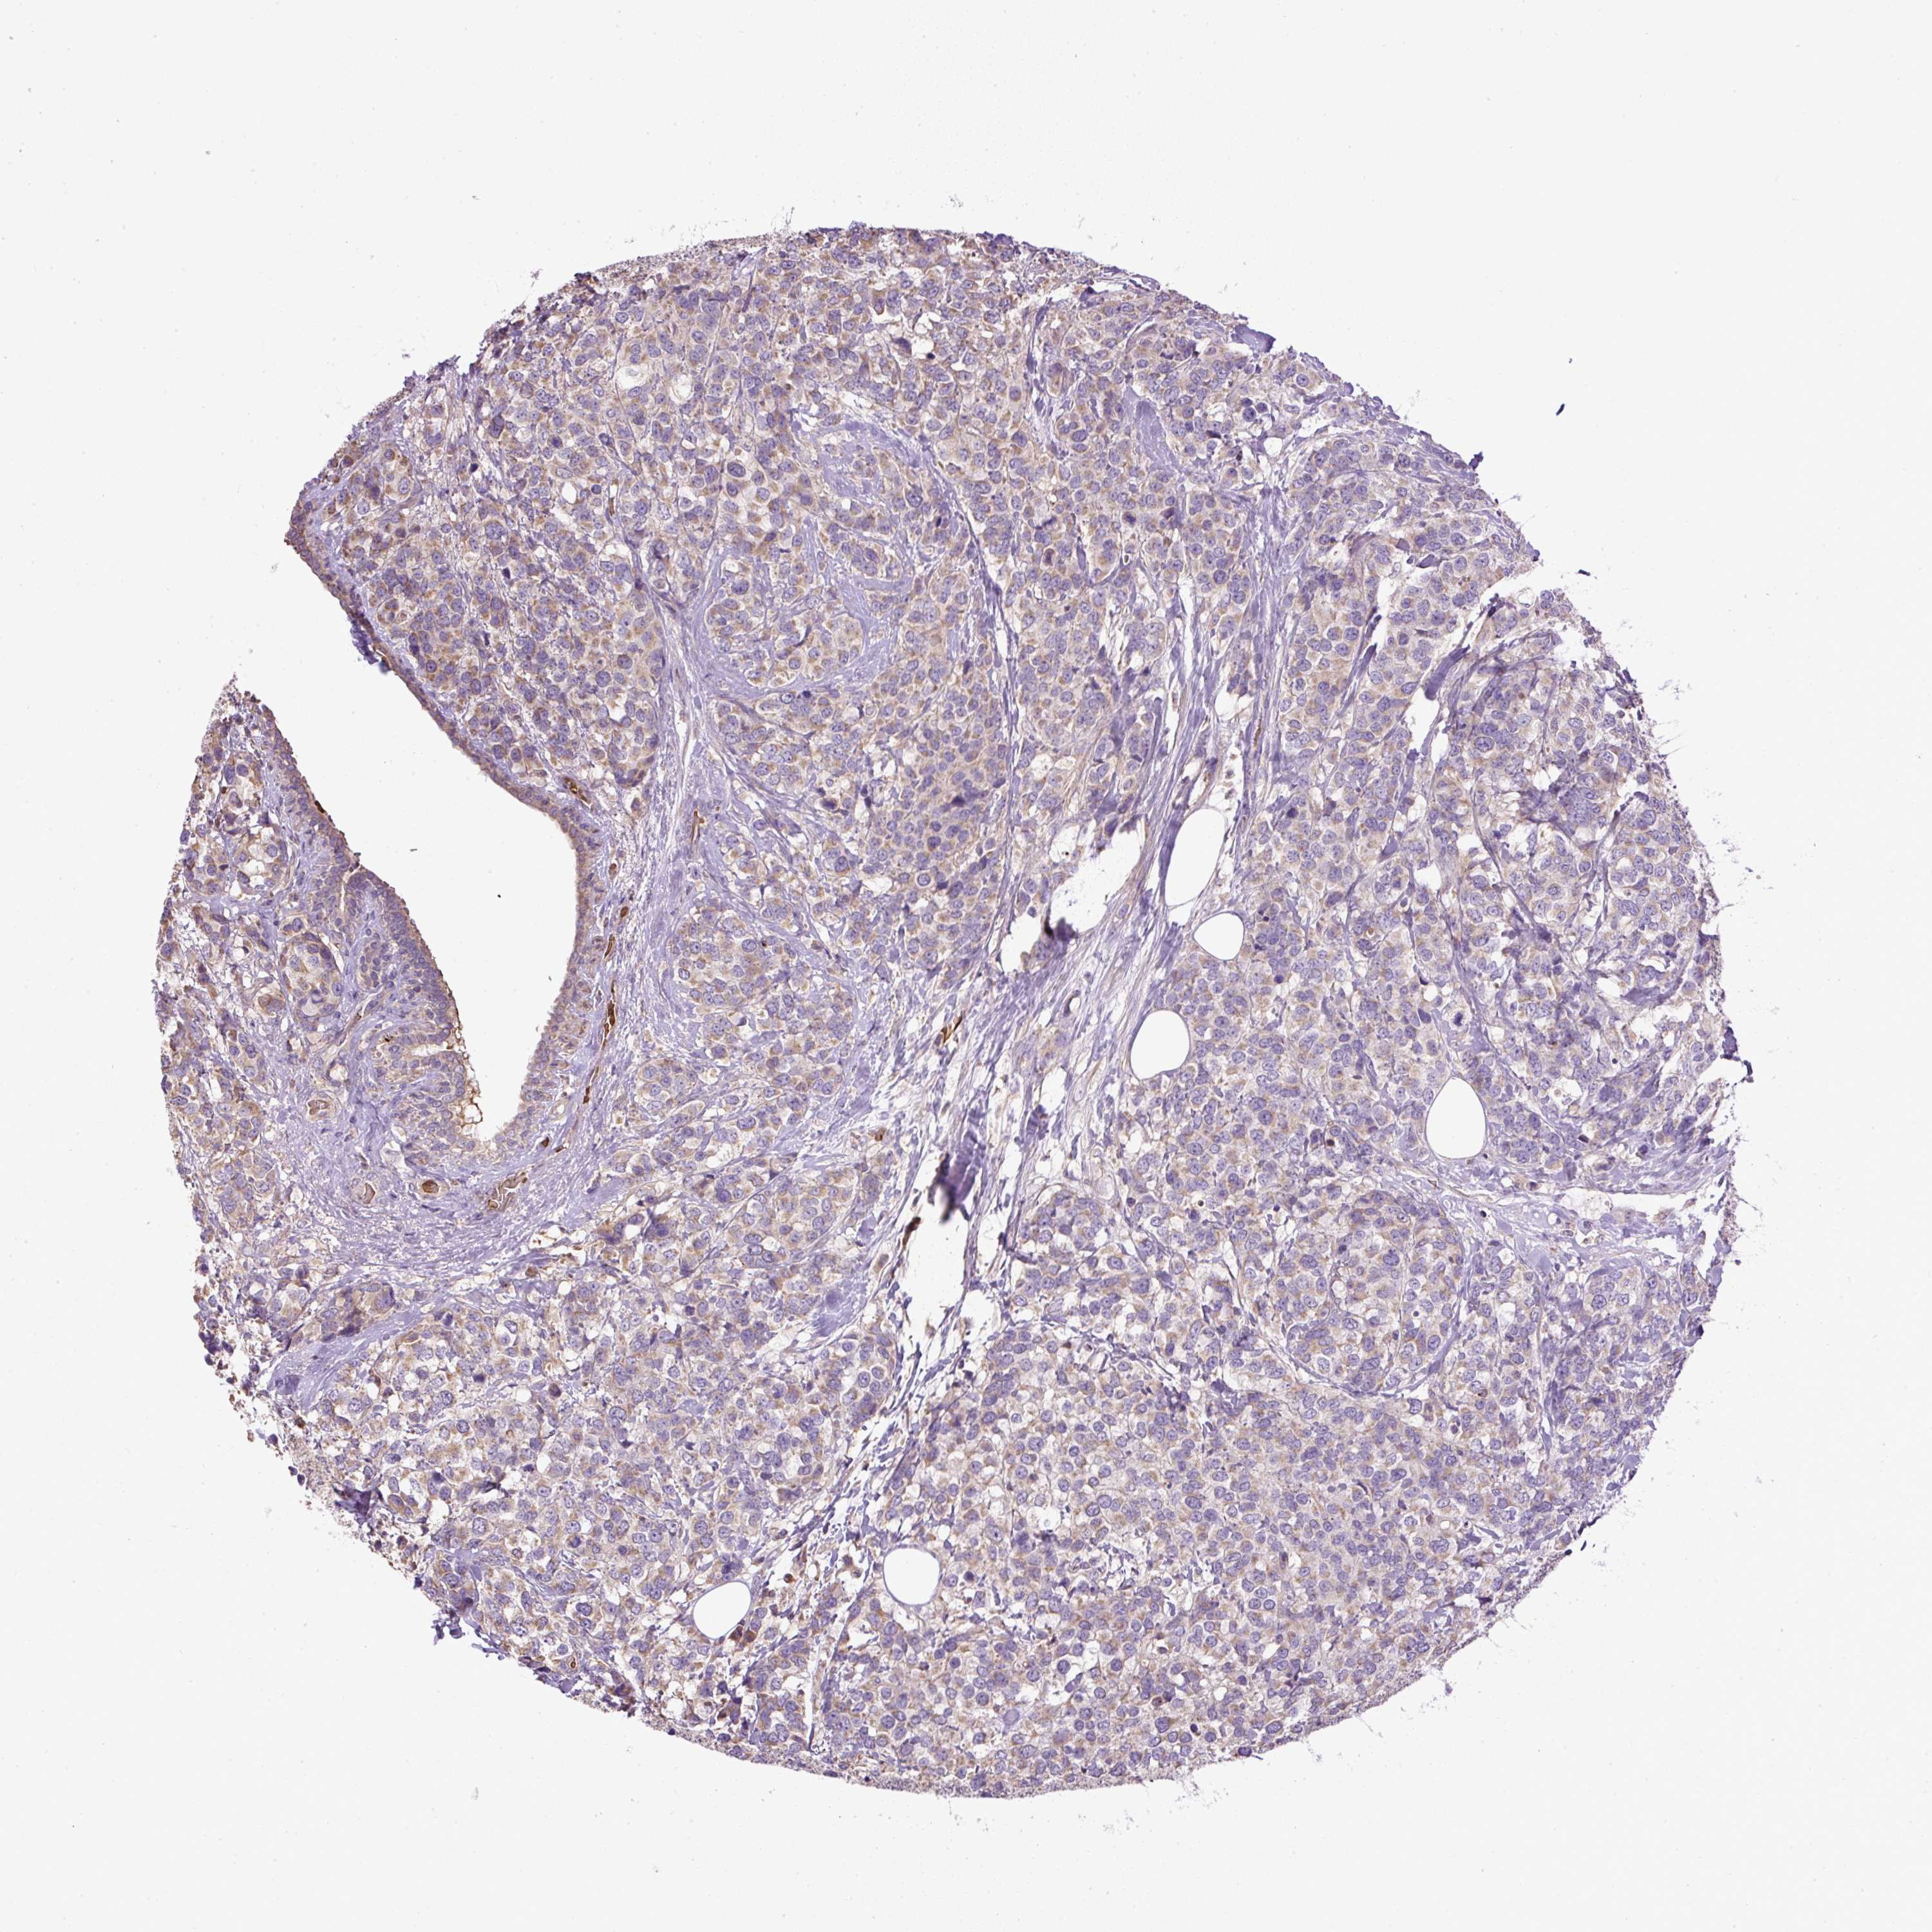

BRCA TCGA BRCA VALIDATION PROTEIN EXPRESSION